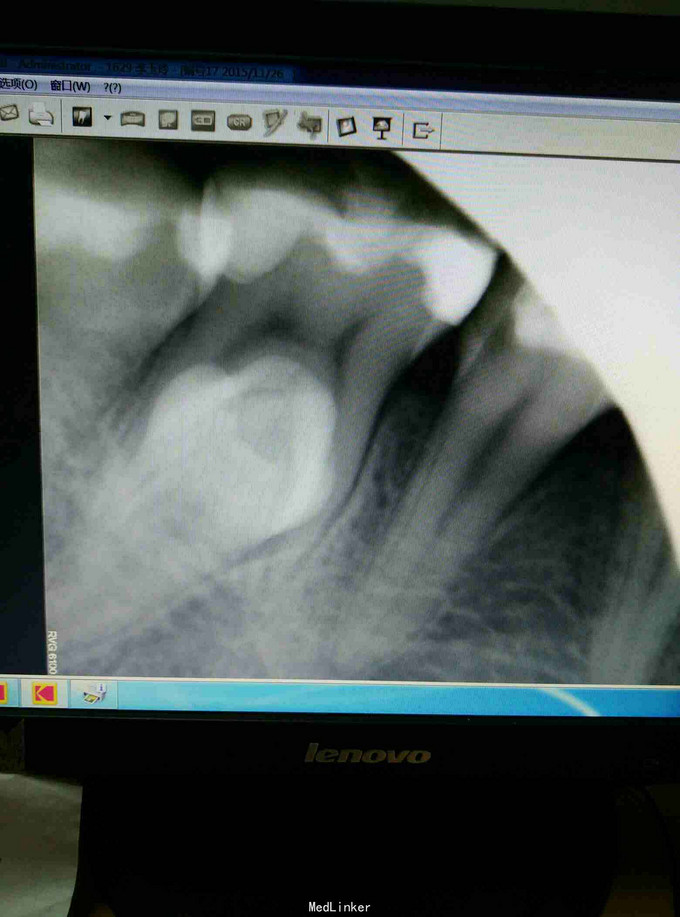

体查见46舌侧一骨性隆起,扪诊质硬。粘膜表面稍白。余检查无特殊。予患者口腔全景片检查,排除颌骨病变。提示46根部高密度影,根交低密度影。于是再次行根交片检查,结果提示:46根部多生牙。